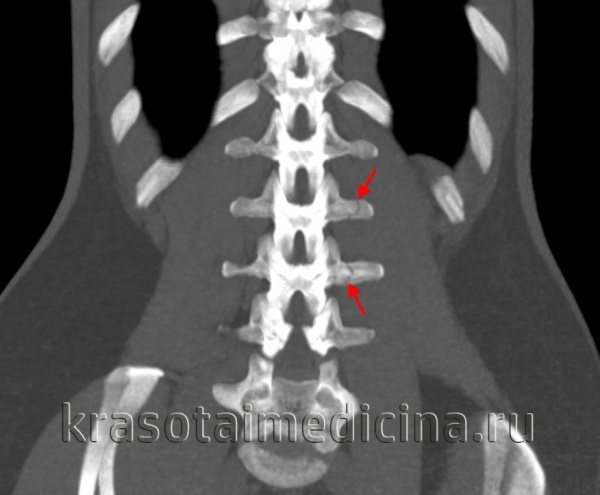

(Слева) КТ, фронтальный срез: латеральная дислокация боковой массы С1. Верхушка зубовидного отростка находится у края большого затылочного отверстия в связи с потерей высоты атланта. Обратите внимание на повреждение атланто-затылочного сустава и вывих в дугоотростчатом суставе С1-С2. Также здесь имеет место перелом левой суставной колонны С2.